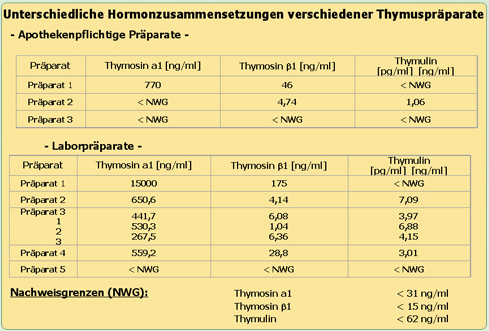

Bei der Behandlung von Krebserkrankungen ist es wichtig, dass bestimmte Thymushormone (Thymosin alfa 1, Thymosin Beta 4 und Thymulin) ausreichend vorhanden sind.

Diese sind entscheidend für die Aufrechterhaltung und Wiederherstellung

einer funktionsfähigen Abwehr. Sowohl die Thymushormone der verschiedenen Thymuspräparate als auch die von ihnen erwünschte Aktivierung von Abwehrfunktionen sind im Labor meßbar.

( Fragen Sie Ihren Therapeuten welche Thymushormon- zusammensetzung die verabreichten Präparate haben).

Der Thymusgesamtextrakt THX hat die höchsten Anteile an den wichtigen immunregulierenden Thymushormonen und eine sehr gute im Labor meßbare T-Lymphotzytenaktivierung zur Folge.